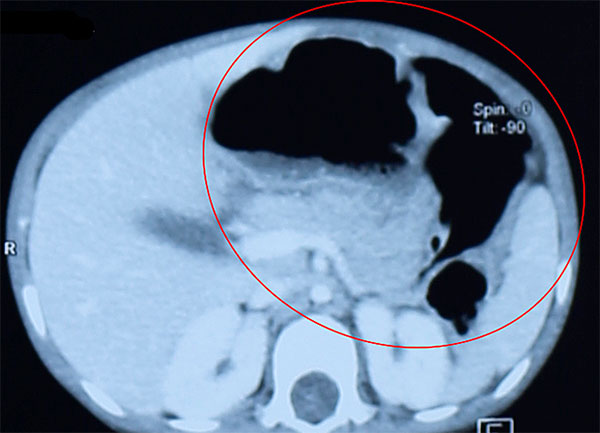

Bệnh nhi khám tại Bệnh viện Quốc tế Hoàn Mỹ Vinh ngày 14/6 với thể trạng suy dinh dưỡng nặng, nôn ói nhiều, thậm chí nôn ra thức ăn của ngày hôm trước. Tình trạng nôn ói diễn ra thường xuyên từ khi bé bắt đầu ăn dặm. Bé đã 25 tháng nhưng chỉ nặng 7 kg, gia đình lo lắng đưa đi khám nhiều nơi nhưng chưa giải quyết được bệnh.

Bác sĩ thăm khám, thực hiện các kiểm tra cận lâm sàng, phát hiện dạ dày bệnh nhi giãn to, có chứa nhiều thức ăn mặc dù nhịn ăn từ chiều hôm trước. Bệnh nhi được chẩn đoán tắc tá tràng không hoàn toàn do màng ngăn niêm mạc, chỉ định phẫu thuật.

Vì thể trạng yếu nên bé được điều trị hồi phục điện giải và bổ sung dinh dưỡng trước mổ. Đến 21/6, các bác sĩ tiến hành phẫu thuật trong 60 phút, cắt bỏ màng ngăn tá tràng và tái lập lưu thông đường tiêu hóa. Sau mổ hai ngày, bé đã có thể ăn uống bình thường và vừa xuất viện, hẹn tái khám sau một tháng.